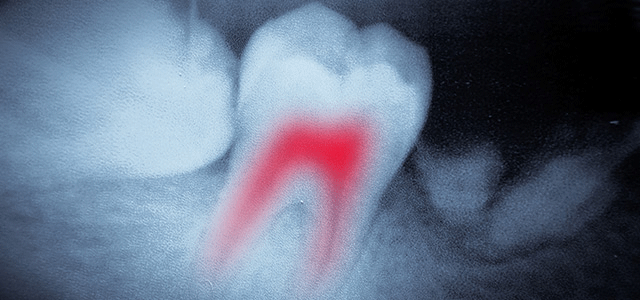

Root Canal Therapy

A root canal is something that we don’t mind as long as it happens to someone else.

Root canal therapy has existed for centuries and actually was first performed in ancient civilizations – although most often only the nobility and the very wealthy were treated.

Root canal treatment is used to save teeth which would otherwise need to be removed.

It is needed when the blood or nerve supply of the tooth (known as the pulp) is infected through decay or injury.

Sometimes, due to trauma or decay the “nerve” inside the tooth dies off (please do not confuse that with your “tooth” being dead, that is simply not true!). Any passing bacteria find this a source of nourishment and proceed to munch on the dead nerve and quickly reproduce. Your body can’t do anything about this infection because along with the nerve dying, the blood supply to the tooth dies off too, so the body can’t send in some antibacterial cells (white blood cells) to attack the bacteria. Eventually, the bacteria start to spill out of the tooth and into the tiny space between the tooth and the jawbone. This starts an abscess, the body reacts to the invasion by pouring in defensive cells, which kill most of the bugs in the area, but still can’t get to the source of the problem, which is in the tooth.

Some indications for a root canal are:

- Pain while biting

- Sensitivity to hot or cold

- Deep decay

- Blunt injury to the tooth

- Infection

What is root canal therapy?

Your dentist will thoroughly examine your tooth to determine if the nerve is infected. The exam includes x-rays and checking the health of the tooth with a pulp tester. Additionally your doctor may also apply cold and heat, tap on the tooth to see if sensitive or press gently on gums around tooth to check for pain.

The treatment can take from one to three visits during which typical treatment involves:

- Making an opening through the crown of the tooth and into the pulp chamber

- Removing the pulp. The root canal is cleaned, enlarged and shaped to a form that can be filled.

- (Optionally) Placing medication into the pulp chamber and root canal to help get rid of any germs and prevent infection.

- Placing a temporary filling in the crown opening to protect the tooth before your next visit. Alternatively, your doctor may leave the tooth open for a few days to drain.

- Filling and sealing the pulp chamber and root canals.

- Removing the temporary filling, followed by cleaning and filling of the pulp chamber.

- And finally, placing a gold or porcelain crown over the tooth.